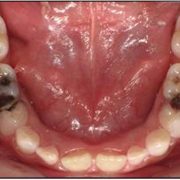

- زبر و خشن شدن لبه دندانها و روی آنها

- گسترش پوسیدگی دندان

- شکسته شدن دندان ها به صورت ترک خوردگی ریز یا تراشهای